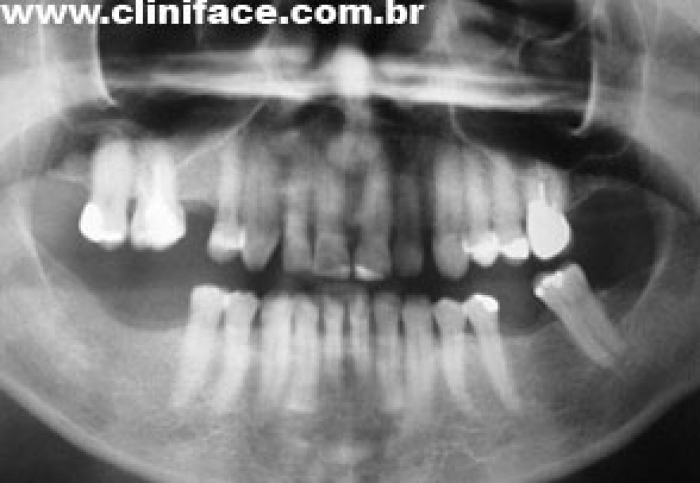

Próteses fixas sobre implantes instaladas